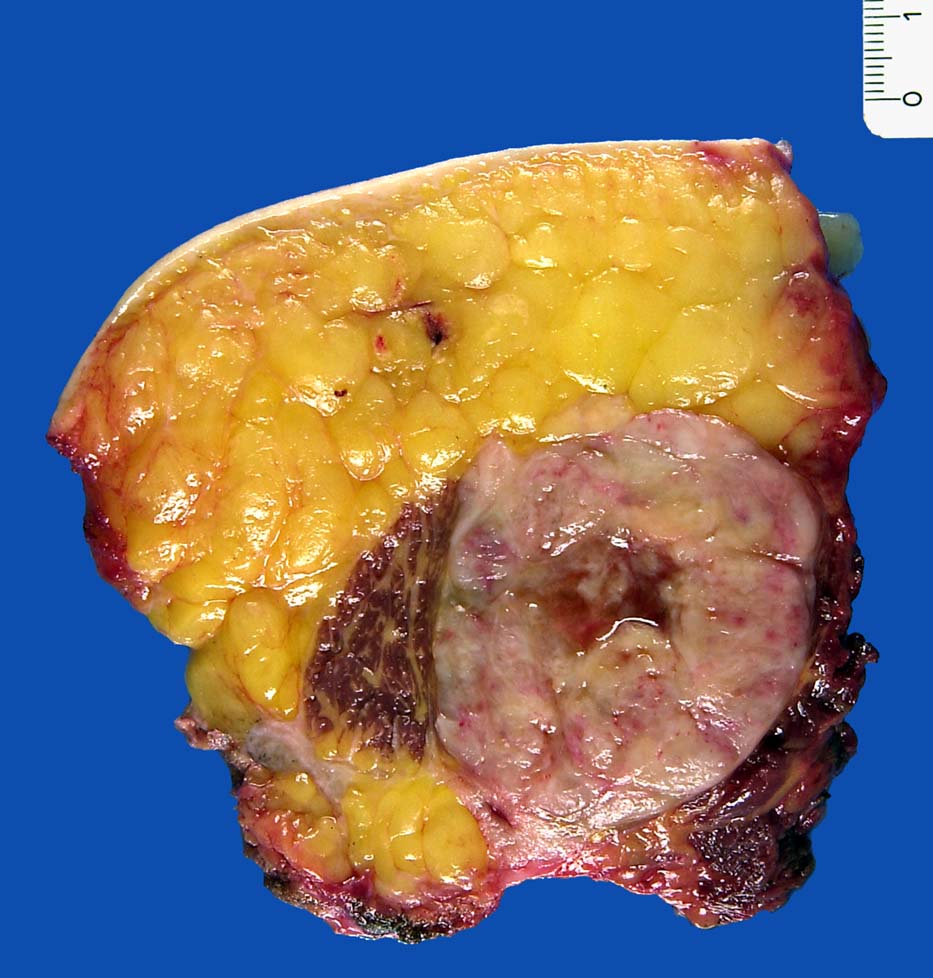

Makroskopie

Befund

Pathologischer Befund